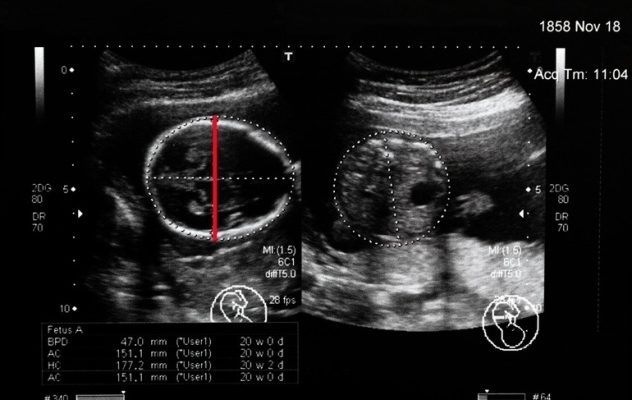

Биколорный размер – это расстояние между наиболее выступающими точками теменных костей головки плода. Этот коэффициент соответствует ширине головы ребенка. Как правило, ультразвуковое исследование проводят через гастроэнтерит. Только в случае плохой видимости применяют трансвагинальный метод, имеющий лучшую разрешающую способность.

Основным принципом исследования ДГПЖ является прохождение ультразвуковой волны через головку плода в горизонтальной плоскости. После получения четкого изображения измеряют расстояние между наружной поверхностью верхнего контура и внутренней поверхностью нижнего контура полученного эхографического изображения. Таким образом получается двухцветное значение с точностью до 1 мм. Нюансы УЗИ важны только для диагностов.